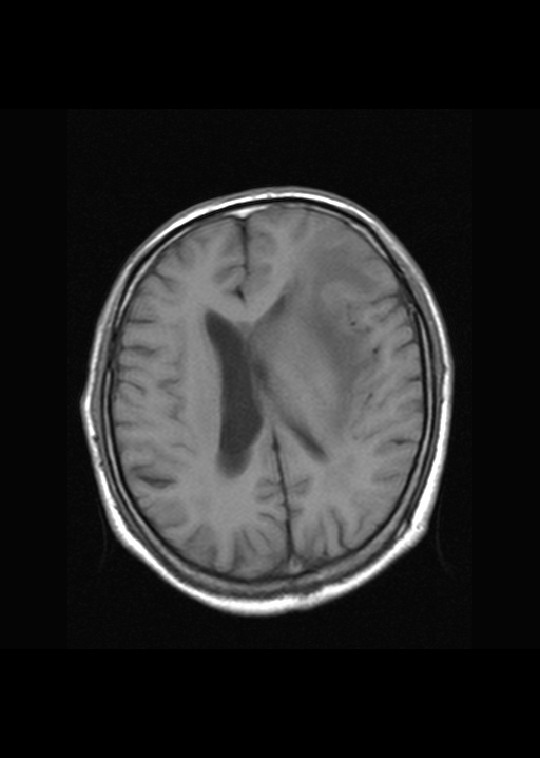

左侧基底节区病灶t1wi呈不均匀稍低信号,t2wi呈稍高信号,周围伴有水肿。增强扫描呈均匀团块样或者抱拳样明显强化,相邻的柔脑膜亦见线样强化。首先考虑淋巴瘤。可惜没有ct平扫,如果ct平扫病灶呈高密度,那么更支持pcnsl的诊断。

左侧基底节区长t1长t2异常团块状信号,增强呈明显均一强化,水肿明显,挤压侧脑室前脚,本人考虑为胶质瘤可能性大。

淋巴瘤可能性大,考虑侵犯侧脑室

左侧基底节区病灶t1wi呈不均匀稍低信号,t2wi呈稍高信号,周围伴有水肿。增强扫描呈均匀团块样或者抱拳样明显强化,首先考虑淋巴瘤。